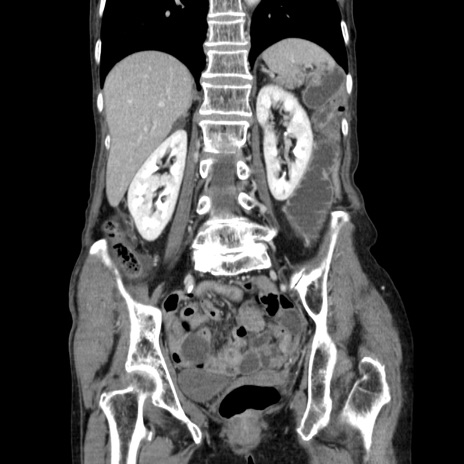

症例25(冠状断像)

【症例】80歳代女性

【主訴】胸のつかえ感

【現病歴】約9時間前に食後から胸のつかえた感じあり、嘔吐あり、来院。

【既往歴】胃癌(全摘)、胆摘、虫垂炎

【身体所見】心窩部に圧痛あり、反跳痛なし。

【データ】WBC 5700、CRP 0.05